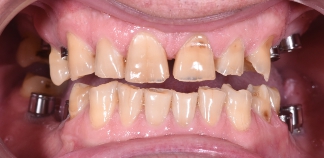

До лечения

Жалоба на боль при накусывании.

Как лечили

Зуб удален из-за трещины корня. На его место установлен одномоментно имплантат и временная коронка. Киста пролечена, перфорация десны ушита. Через 2 месяца установлена постоянная коронка.